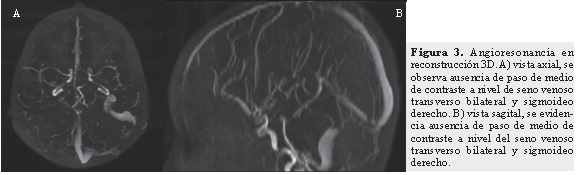

Se realizó Doppler arterial transcraneano y se encontraron, a nivel de arterias cerebrales medias, cambios compatibles con estado de hiperperfusión en las regiones izquierdas que pueden estar en relación con edema cerebral de ese lado. En la RNM cerebral simple y con gadolineo más angioresonancia se evidenció trombosis de senos venosos cerebrales profundos (parcial de seno longitudinal superior, completa de seno venoso transverso de predominio izquierdo, parcial a nivel de senos venosos sigmoideos y trombosis a nivel de la confluencia de los senos) (Figuras 1 y 3). Se evidenciaron accidentes cerebrovasculares (ACV) isquémicos venosos gangliobasales izquierdo y derecho, talámico izquierdo y hemisferios cerebelosos. Así mismo, se vio edema cortical en las regiones occipitales bilaterales y hemisférica izquierda por proceso de congestión venosa veno-capilar y se observaron áreas de necrosis laminar cortical fronto-parietales izquierdas. En la RMN cerebral de control hay evidencia de ACV isquémico en los globus pallidus bilaterales de mayor compromiso en región gangliobasal izquierda (Figura 2) y ACV isquémico en el mesencéfalo a nivel de los pedúnculos cerebrales de forma bilateral, sin evidencia de progresión de la trombosis con respecto a la RNM previa.